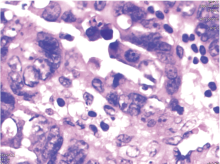

鼻咽低级别乳头状腺癌(LGNPPA)是鼻咽癌的一种罕见病理类型。现报道右侧鼻腔LGNPPA病例1例,患者鼻内镜下肿物摘除术后行同步放化疗,随访3年无复发及远处转移。